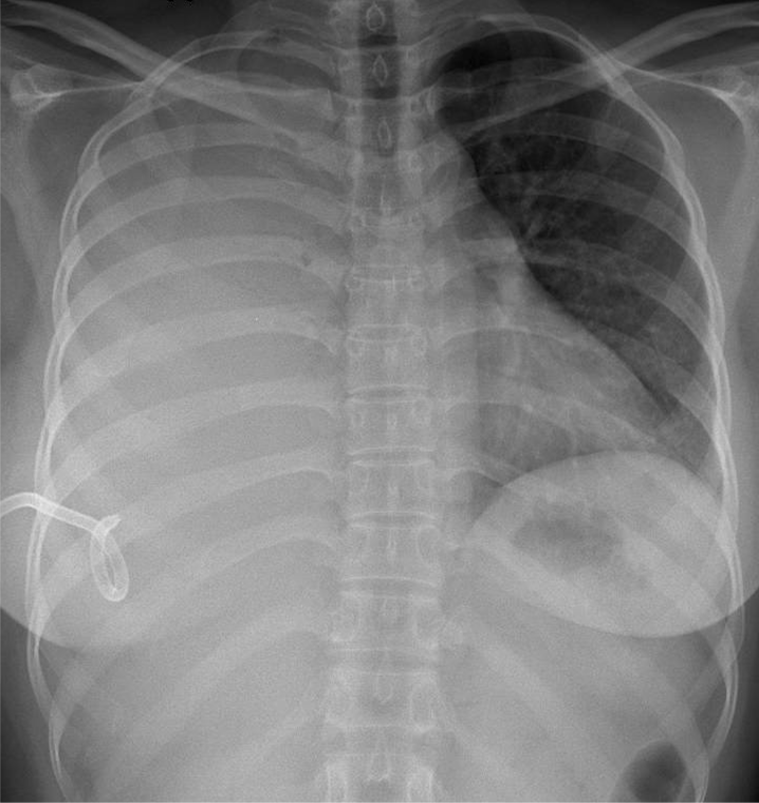

1-Tràn dịch màng phổi (T) lượng nhiều đẩy bóng tim và trung thất lệch(T) 2-Màng phổi (P) đang dẩn lưu